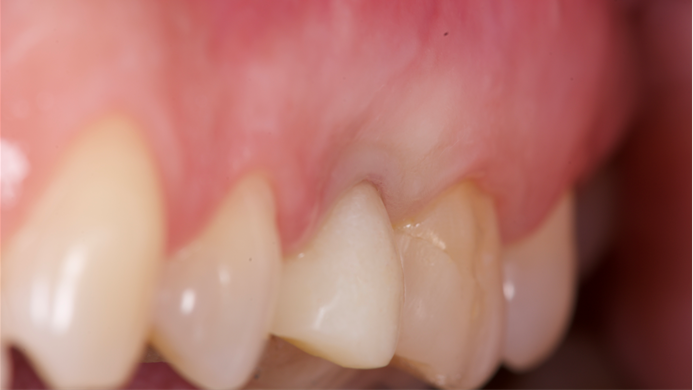

Clinical case: Extraction, immediate implant placement, & provisionalization

- Courtesy of Dr. Iulian Filipov, Romania -

AnyRidge, R2GATE, guided surgery, immediate placement, immediate provisionalization, initial stability, Dr. Iulian Filipov, #25, maxillary posterior, immediate loading, Mega ISQ

AnyRidge implant system, R2GATE, MEGA ISQ, Digital prosthesis